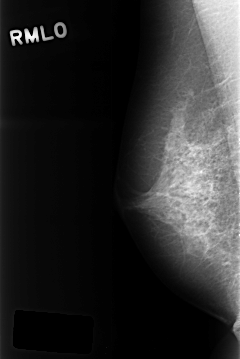

C_0320_1.RIGHT_MLO

RIGHT_CC LINES 4360 PIXELS_PER_LINE 2872 BITS_PER_PIXEL 12 RESOLUTION 50 NON_OVERLAY

RIGHT_MLO LINES 4304 PIXELS_PER_LINE 2872 BITS_PER_PIXEL 12 RESOLUTION 50 NON_OVERLAY